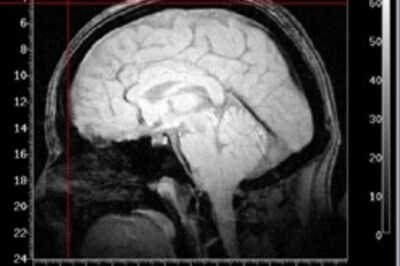

Imaging techniques may spot dementia

Study identifies structural and metabolic brain changes that predict dementia on normal older adults.